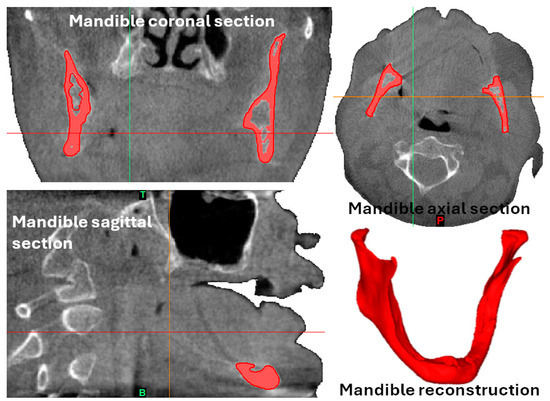

2.1. Design of Maxilla and Mandible Recreations